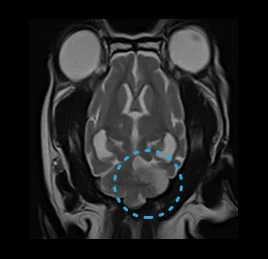

• 수막뇌염

• 허혈성 소뇌경색

• 이도 염증 - 내/중/외이염

• 허혈성 척수병증

• 척수공동증

• 뇌수두증

• 후두골 이형성 증후군

• 디스크 탈출증

• 뇌하수체 종양

• 뇌종양

• 뇌출혈

• MRA- 뇌혈관 조영술